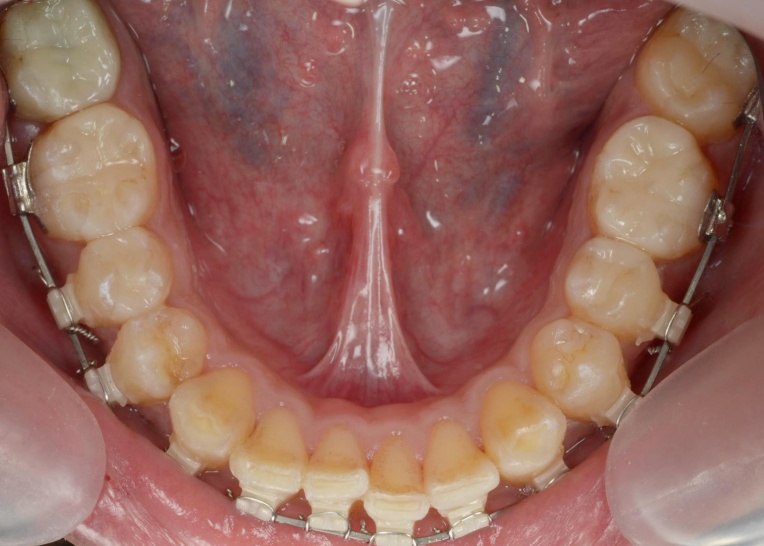

この状態で下顎にのみワイヤーを装着し、安定した下顎の位置をキープしながらワイヤー矯正治療へ移行します。

矯正治療は、顎の痛みや噛み合わせの違和感などが落ち着き、安定した状態で進めることが重要です。

また、上顎には上下の噛み合わせの前後関係を整えるための補助装置「顎間ゴム」を使用し、噛み合わせを正しい位置関係へ導く「咬合(こうごう)誘導」を行っています。